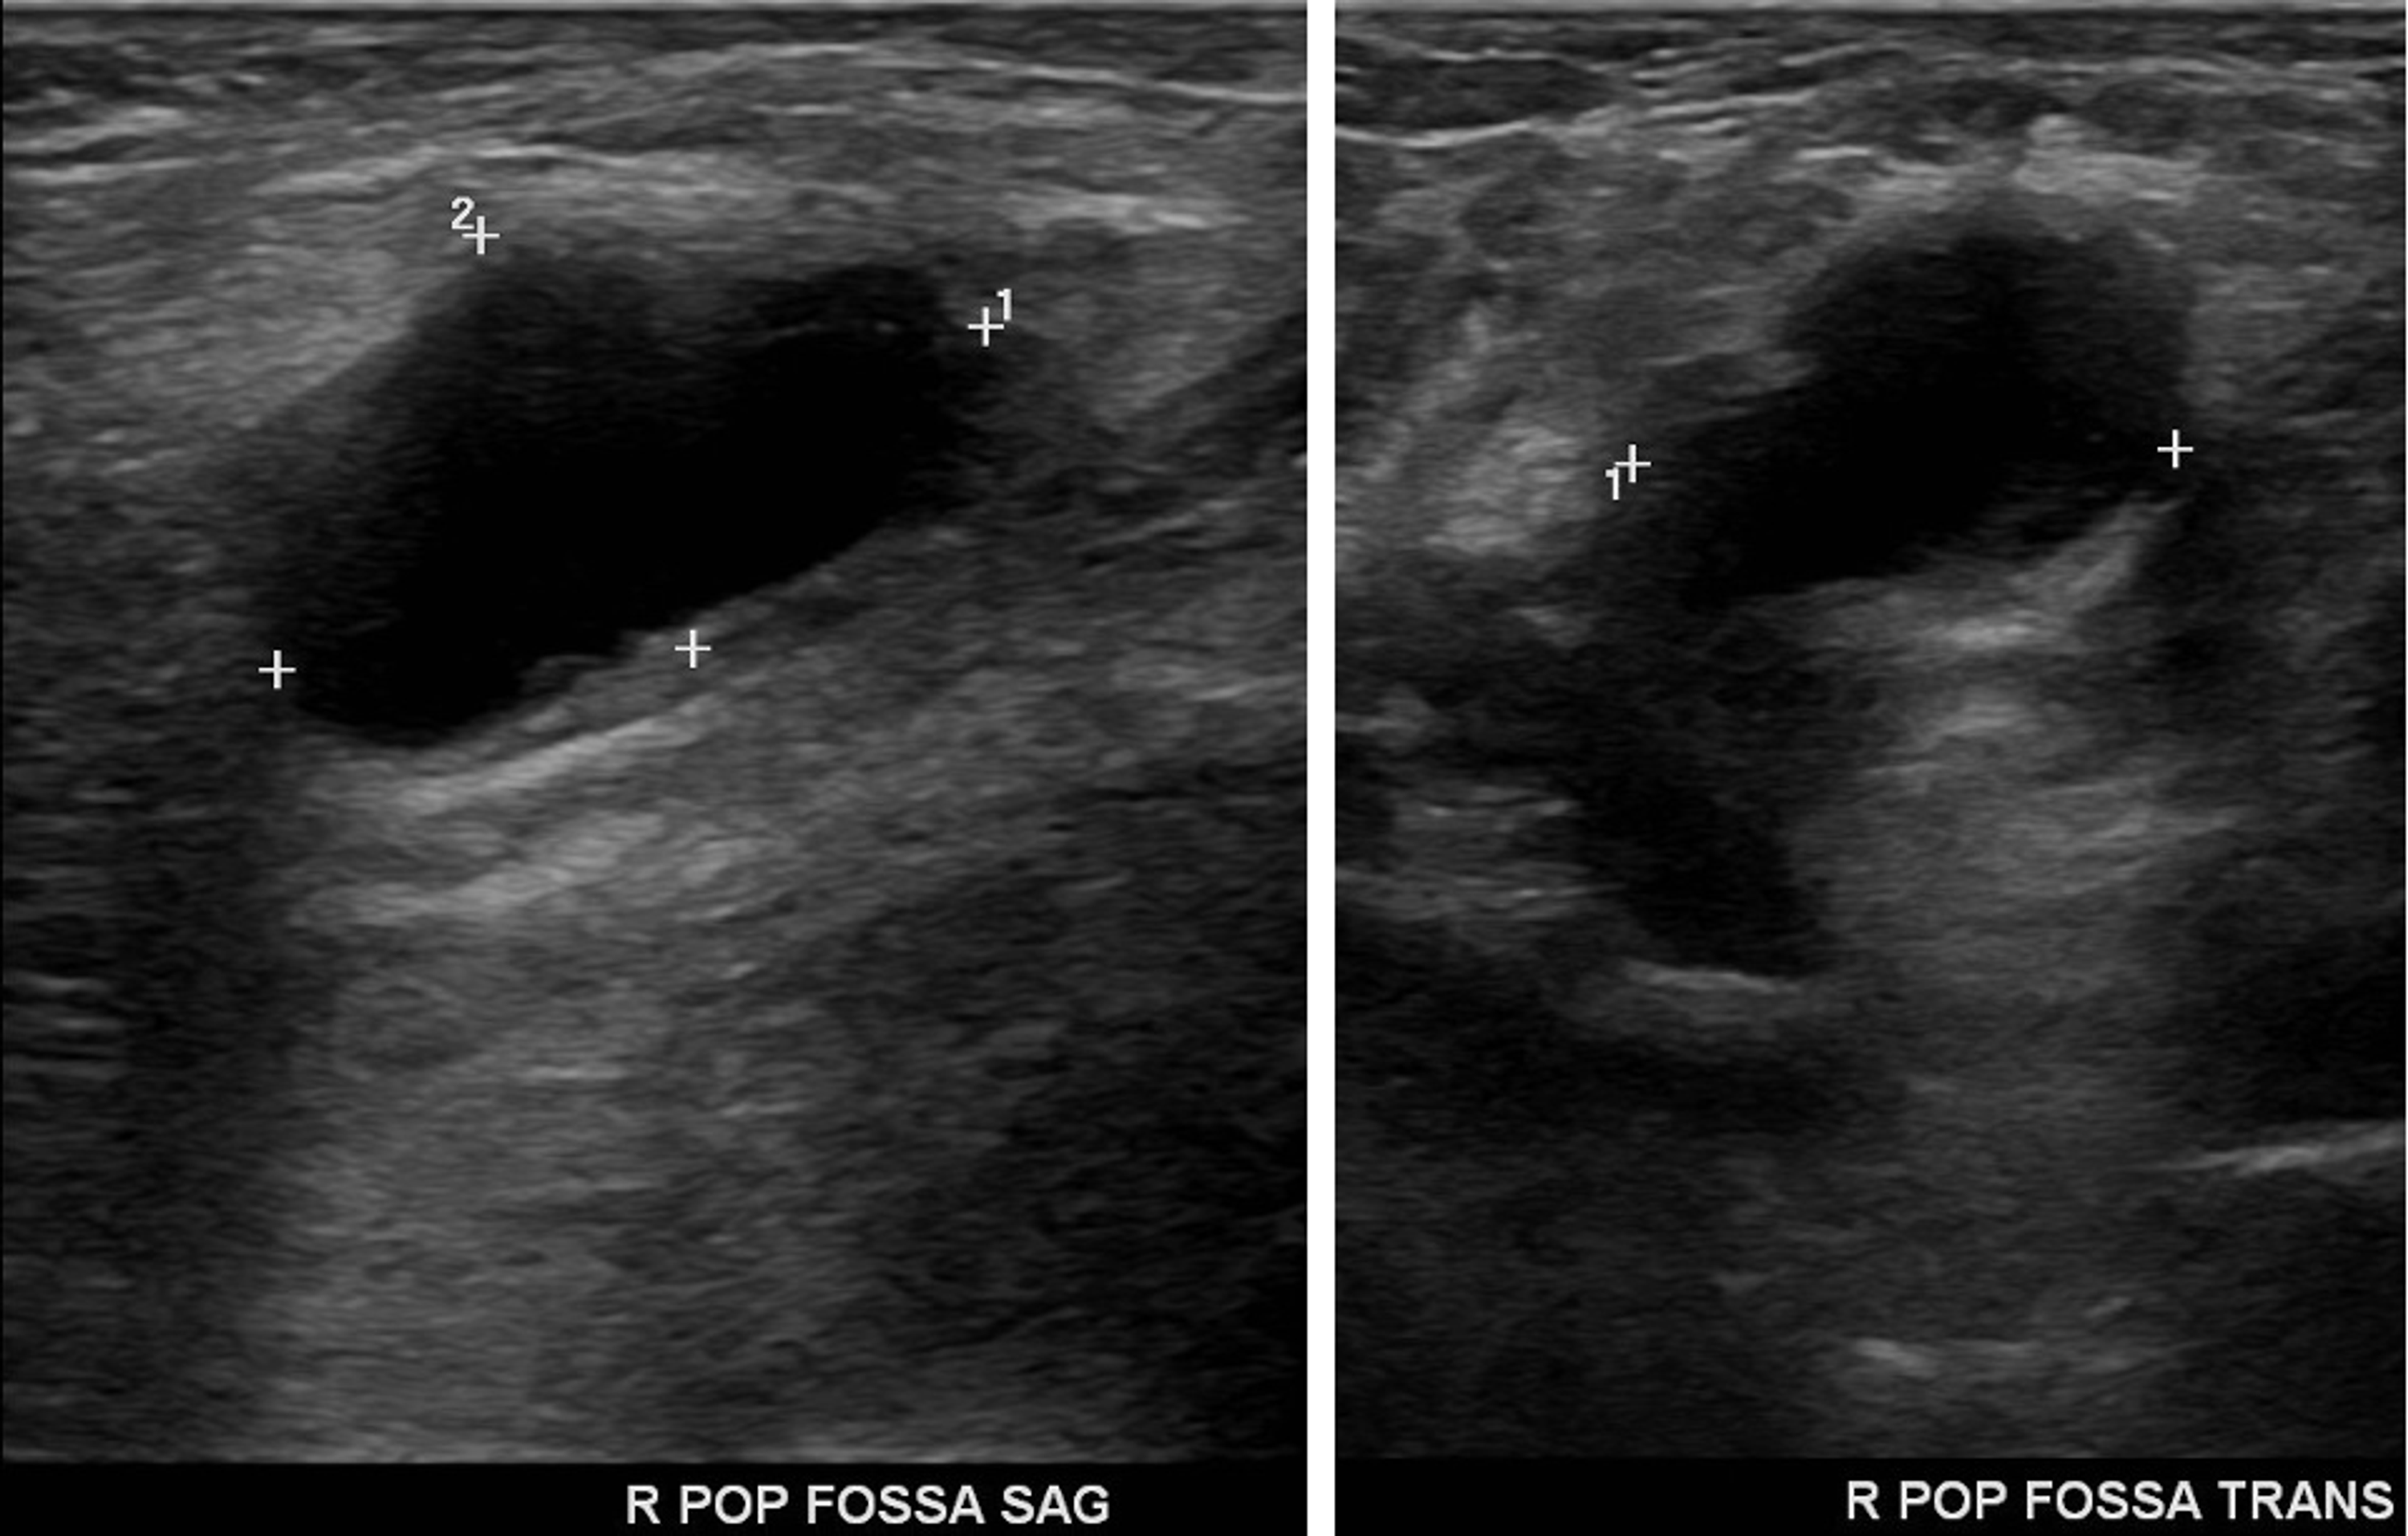

Baker's Cyst Behind Knee Ultrasound . Baker cysts are the most common pathologic finding in the sonography of the popliteal fossa. The most obvious symptom of a baker cyst is the bump that. symptoms and causes. baker cysts can be associated with conditions such as osteoarthritis of the knee, meniscal tears, rheumatoid arthritis, charcot joints,. Treating the cause usually provides. They typically result from a problem. baker’s cysts, also known as popliteal cysts, form a lump at the back of the knee that can cause stiffness and discomfort. They have a wide range of. popliteal cysts in adults are often associated with osteoarthritis, inflammatory joint disease, or joint injury. What are baker cyst symptoms?

The Sonographic Spectrum of Baker Cysts Tony Y. Li, 2018 Baker's Cyst Behind Knee Ultrasound Baker cysts are the most common pathologic finding in the sonography of the popliteal fossa. symptoms and causes. They have a wide range of. baker cysts can be associated with conditions such as osteoarthritis of the knee, meniscal tears, rheumatoid arthritis, charcot joints,. Treating the cause usually provides. They typically result from a problem. popliteal cysts in. Baker's Cyst Behind Knee Ultrasound.